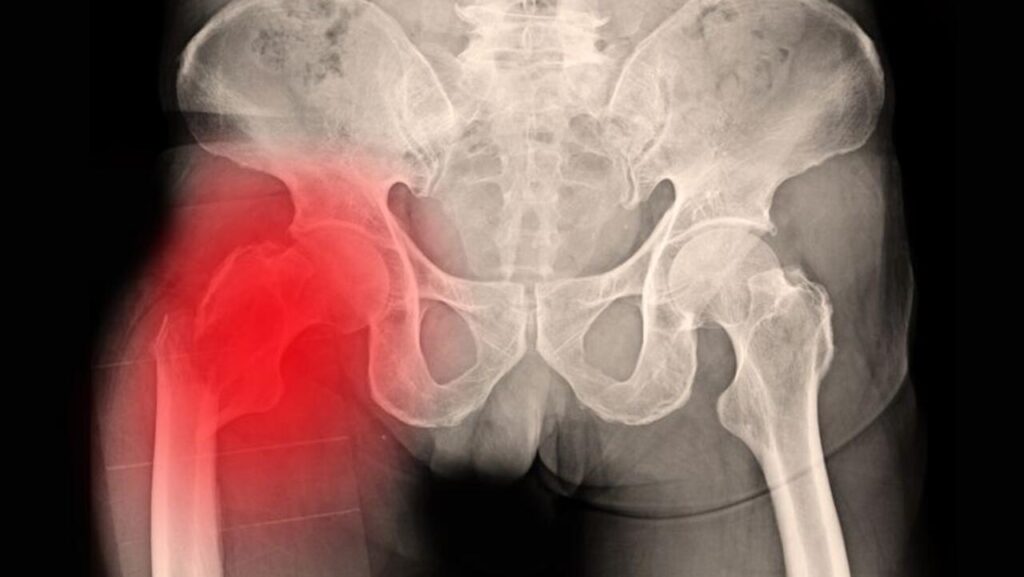

Bu durumu yaşayan bir kişi genellikle ayağa kalkmayı veya yürüme girişiminde bulunmayı denediğinde şiddetli bir ağrı hisseder. Ağrı genellikle kasık veya kalça bölgesinde yoğunlaşır. Kırık nedeniyle kişinin hareket etmesi zorlaşır. Bacak hareketleri kısıtlanır ve oturup kalkma ya da yürüme gibi temel aktiviteler yapılamaz hale gelir. Kırık olan bacak diğerine göre daha kısa görünebilir.

Ayrıca, yaralı bacak genellikle dışa dönük bir pozisyondadır. Kırığın olduğu bölgede şişlik ve ciltte renk değişiklikleri (morarma) görülebilir. Yaşlılarda kalça kırığı olan taraf üzerine basmaya çalışıldığında dayanılmaz bir ağrı oluşur ve kişi ağırlığını o tarafa veremez. Kırık, kişinin rahat bir pozisyonda yatmasını engelleyebilir. Oturma ya da yatakta pozisyon değiştirme sırasında acı artabilir. Yaşlılarda kalça kırığı riskini artıran faktörler arasında osteoporoz, denge problemleri ve kas güçsüzlüğü bulunur. Eğer bu belirtiler gözlemlenirse, zaman kaybetmeden tıbbi yardım alınmalıdır. Yaşlılarda hızlı tedavi gerektiren ciddi bir durumdur. Çünkü hareketsizlik komplikasyon riskini artırabilir.